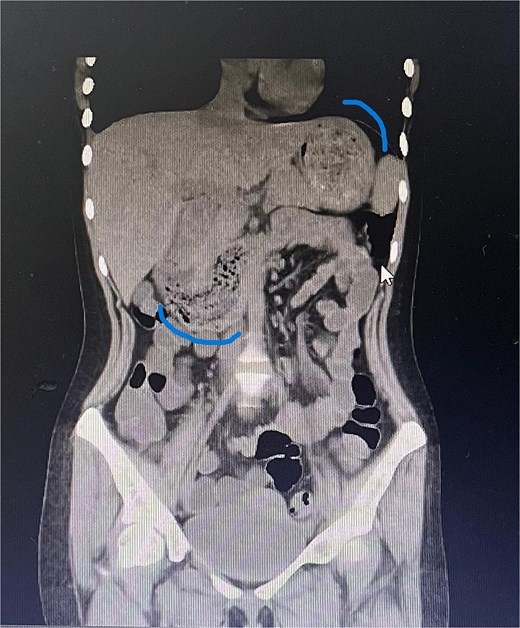

Twelve hours later, she was evaluated by the new emergency surgery team, who found a complete upper obstruction with a foreign body occupying the lower esophagus, the entire stomach, and the entire duodenum (Figs 1–3). A diagnostic laparoscopy (Fig. 10) with gastrotomy was performed (Figs 4 and 5), including foreign body removal (Figs 6 and 7), gastric repair (Fig. 8), and placement of a tubular drain. The findings revealed a large foreign body containing a significant amount of malodorous hair, measuring 30 cm long and 12 cm wide (Fig. 9). Large gauze pads were placed around the stomach to prevent contamination, and the bezoar was removed first through the duodenal area, as this was the area of smallest diameter and least compression. The gastric and esophageal portions were then removed. The foreign body was extracted transumbilically through a small 6 cm incision, protecting the abdominal wall with an isolation device. Gastric repair was performed using a 3–0 continuous suture polydioxanone (PDS) in a single layer. The cavity was irrigated with 3 l of saline solution. The operation was 2 h. Postoperative management included a nasogastric tube on gravity drainage, intravenous piperacillin/tazobactam 4.5 g every 6 h, intravenous tramadol 100 mg every 8 h for analgesia, and intravenous dimenhydrinate 50 mg every 8 h. The patient progressed favorably, with oral intake initiated on postoperative day 4. The tubular drain was removed on day 5 with minimal serous output. Psychiatry discovered that the patient had been diagnosed with trichotillomania in 2014 but refused pharmacological treatment. The patient confirmed that she has suffered from trichophagia since the age of 14. Pharmacological treatment with psychotropic medications and psychological support was initiated. On day 7, the patient was on a soft diet, without a nasogastric tube, with a white blood cell count of 10 740 cells/μl and 0% band neutrophils. Treatment with clomipramine was initiated. She was discharged that day and evaluated 7 days later with no problems.

Sagittal CT image showing the foreign body occupying the gastric cavity and extending into the third and fourth portions of the duodenum.

Sagittal CT image demonstrating the foreign body filling the entire gastric cavity.

Axial CT image showing the foreign body completely occupying the gastric lumen.